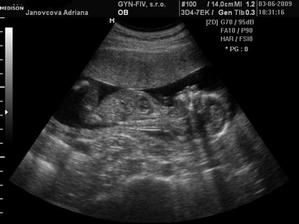

3.6. Uzasny 3D ultrazvuk...Videli sme nasho mimiska... Meriame bez noziciek 10 cm a s nozickami skoro 15 cm... 🙂 A doktor nas prekvapill, ze vraj to bude chlapcek... 🙂 14.7. morfologicky ultrazvuk, vsetko zatial vyzera v poriadku - tesime sa na Andrejka 🙂 12.8. 3D ultrazvuk - ma to 35 cm a 900 gramov, kto je to? No predsa ja Andrejko... 🙂